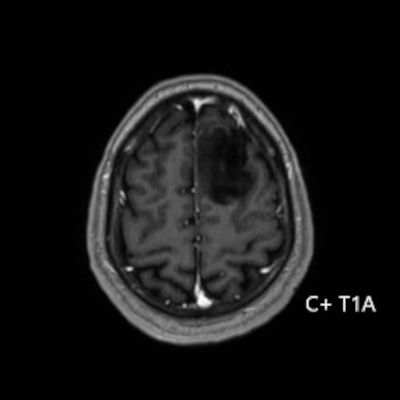

- Sol frontal kortikal-subkortikal yerleşimli aksiyel T2A görüntüde hiperintens sinyal özelliği gösteren (oklar) ve FLAIR görüntüde sinyali ağırlıklı olarak baskılanan (oklar) kitlesel lezyon izleniyor. Lezyon T1A görüntüde hipointens olup post-kontrast T1A görüntüde bu düzeyde patolojik kontrastlanma izlenmiyor (oklar).

- Grade 2 ve 3 tümörlerde çoğunlukla kontrast tutulumu yoktur veya minimal düzeydedir. Grade 4 IDH-mutant astrositomlarda, nekroz veya mikrovasküler proliferasyon varsa heterojen kontrast tutulum gözlenebilir. Kontrast tutulumu her zaman malignite derecesini yansıtmayabilir; bu nedenle biyopsi ve moleküler analiz mutlaka gereklidir.